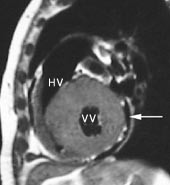

Ved høyre ventrikkel-dysplasi – en arvelig sykdom som kan gi alvorlige rytmeforstyrrelser – sees varierende grader av fettinfiltrasjon i myokard. Spesielt utsatt er høyre ventrikkels frie vegg (fig 8). T1-vektede bilder viser tydelig forskjell på fettvev (hvitt) og myokard (mellomgrått) og er den bildediagnostiske metoden som er best egnet til å vise fettinfiltrasjonen (19). Tilstanden kan også ytre seg som regional eller generell fortynning av høyre ventrikkels frie vegg. De patologiske områdene er ofte hypokinetiske, hvilket kan fremstilles med cine-MR.